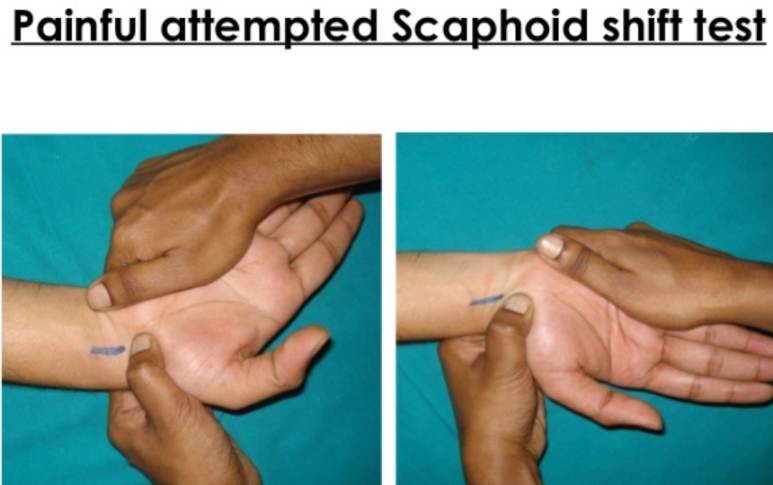

(5) 주상골 이동 검사(Scaphoid shift test)

-

- 주상골을 손등쪽으로 눌렀을때 부딪힘을 느끼기 위함입니다.